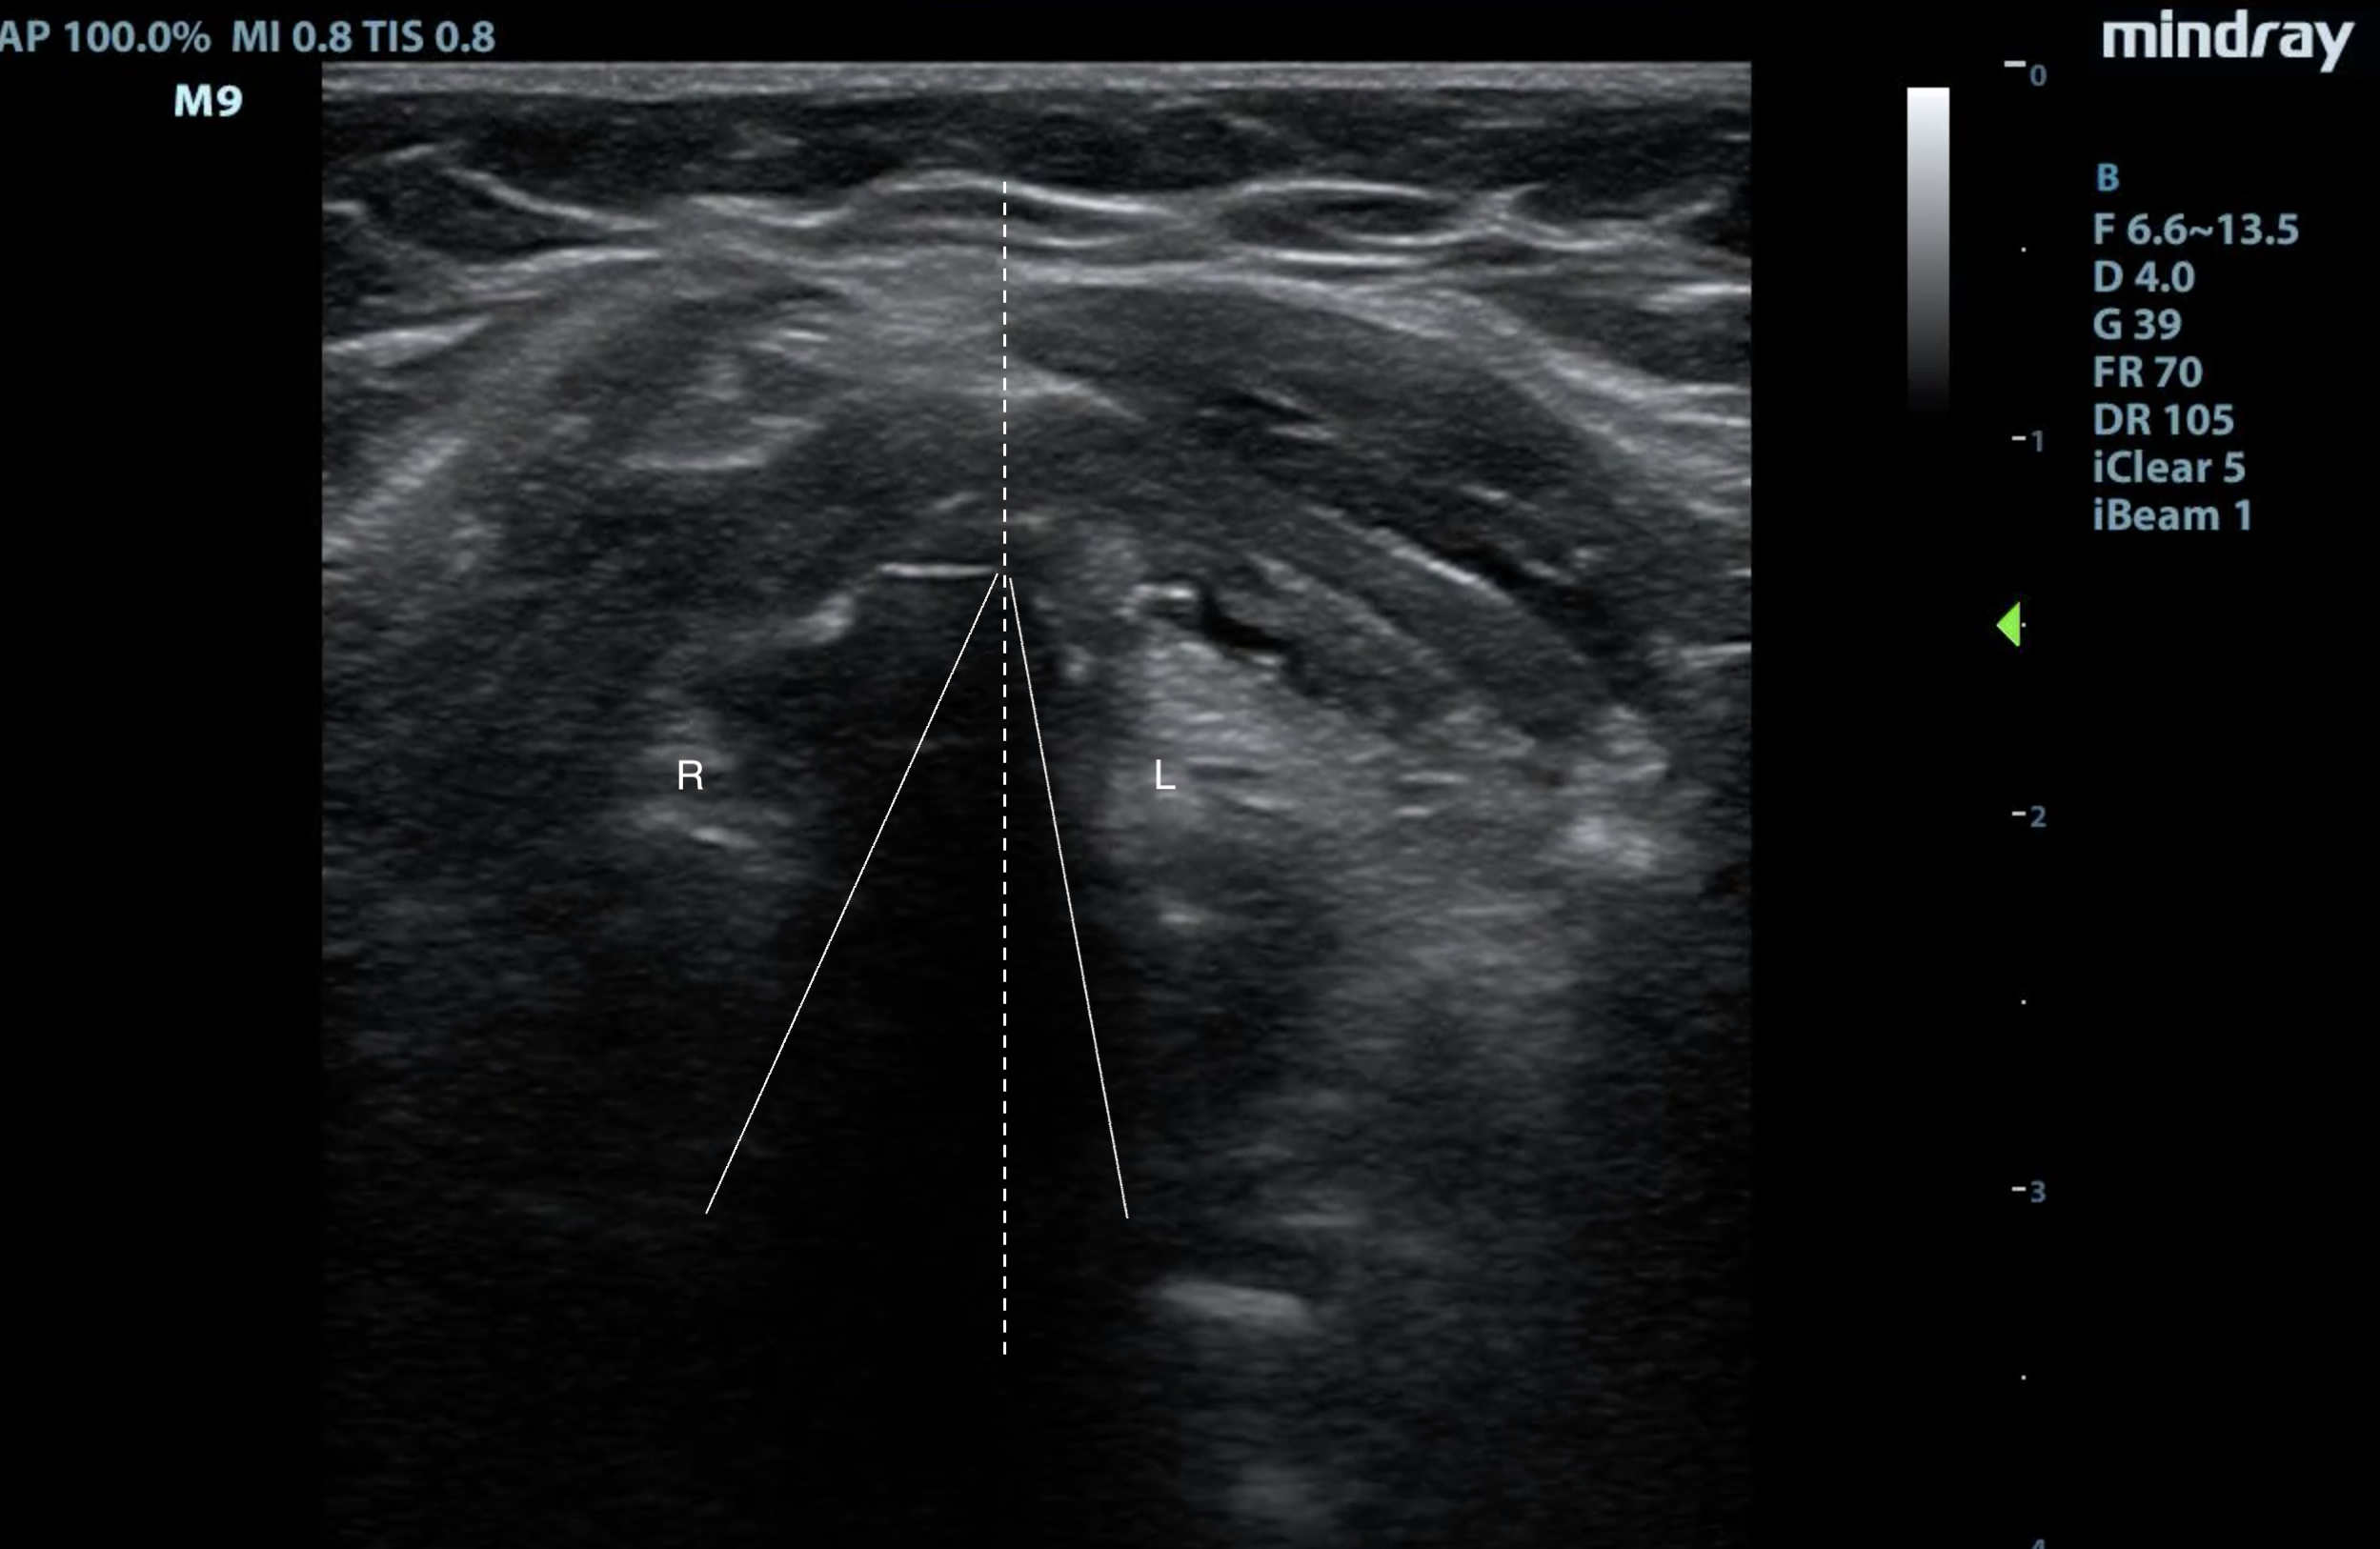

- Figure 9. This patient is trying to phonate, and the right vocal cord (R) is not coming to midline (dotted line), like the left vocal cord (L).